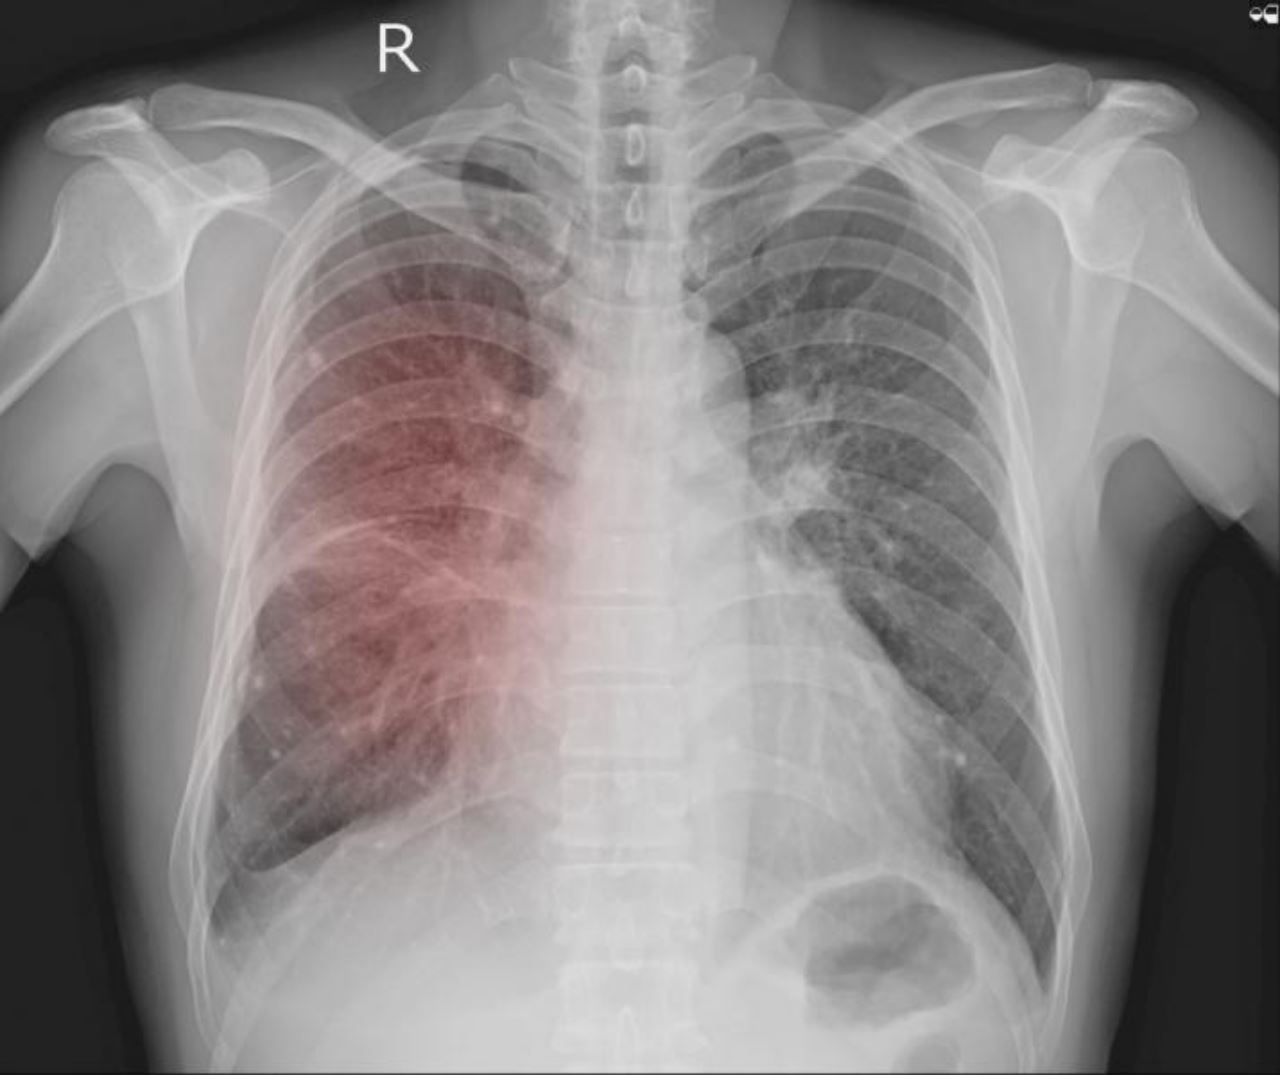

Tiga daripada sembilan individu yang dijangkiti pneumonia atau radang paru-paru misteri dilaporkan meninggal dunia awal bulan ini di Argentina.

Jangkitan misteri itu dilaporkan tertumpu pada sekitar klinik perubatan swasta dekat wilayah barat laut Tucuman.

Pihak berkuasa bagaimanapun tidak menolak kemungkinan ia berpunca daripada COVID-19 dan selesema biasa, namun mereka tetap meneruskan pemeriksaan jangkitan lain.

Mangsa ketiga yang meninggal dunia adalah seorang wanita berusia 70 tahun yang dimasukkan ke klinik itu untuk pembedahan. Beliau juga tidak pernah dijangkiti sebarang penyakit pernafasan sebelum ini.

Rata-rata pesakit yang dijangkiti radang paru-paru misteri itu adalah kakitangan perubatan di pusat terbabit.

Menurut BBC, enam pesakit pertama mula menunjukkan gejala antara 18 dan 23 Ogos. Gejala yang ditunjukkan adalah seperti demam panas, sakit badan dan kesukaran bernafas. Keadaan ini menurut Menteri Kesihatannya adalah sangat serupa dengan COVID-19.